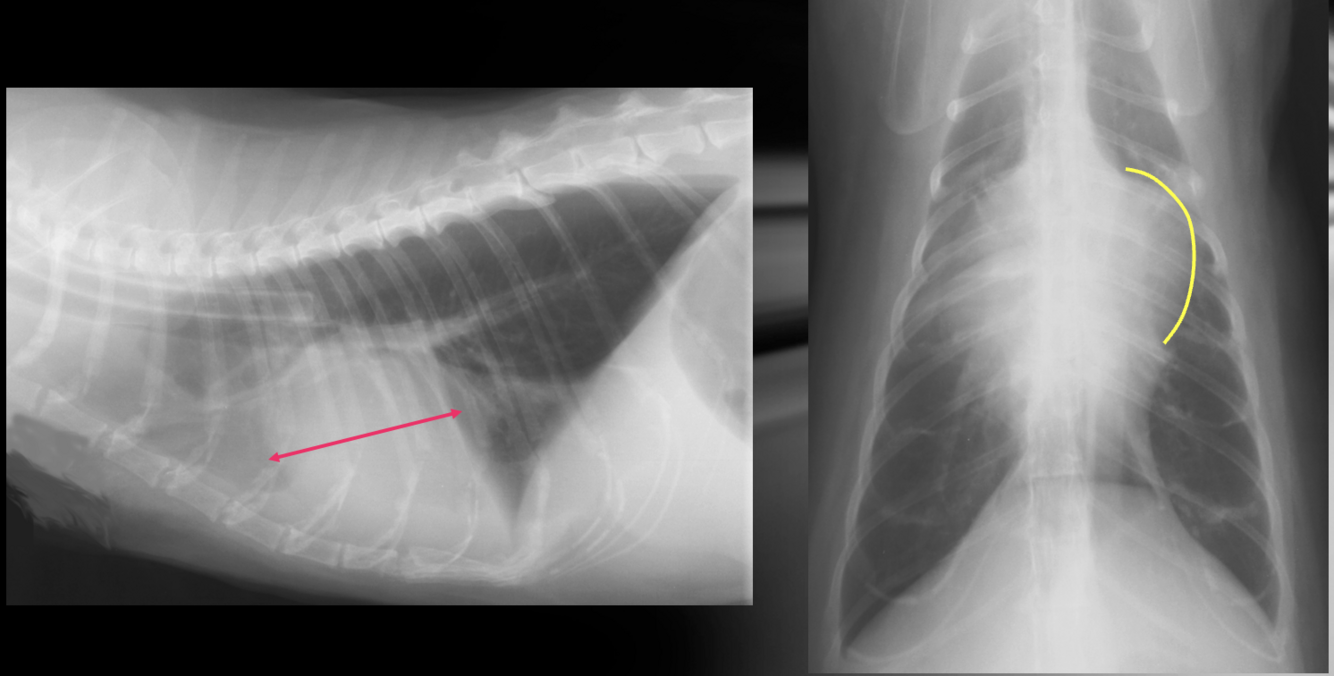

Q

What is shown in these images?

A

(sub)aortic stenosis

-left heart enlargement

-elongation of cardiac silhouette

-increased prominence of aortic arch

What are the findings radiographic findings in subaortic stenosis?

-survey rads may be normal

-left heart enlargement (LVE +/- LAE) due to pressure overload

-very low incidence of left heart failure